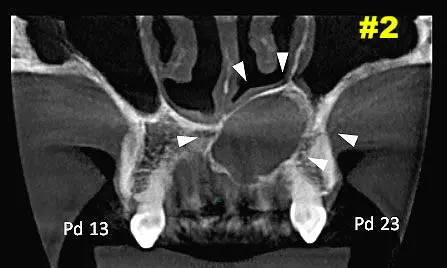

​Dicha lesión vemos que provoca expansión y abombamiento hacia piso de fosa nasal izquierda como también hacia cara palatina. Ver Imagen 2 Y 3. También se puede ver en una navegación  en cortes cada 1mm como se comporta la lesión - ver imágenes 4 y 5 (cortes transaxiales)